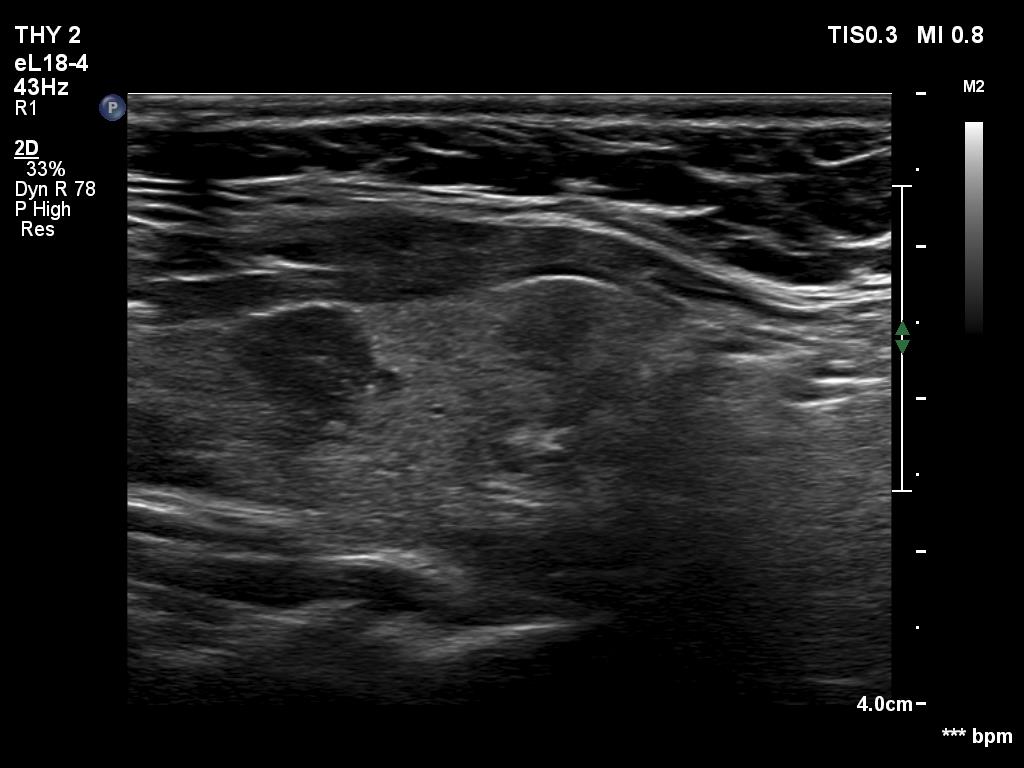

Second examination 2 years later (third rows of images):

Clinical data: The patient had no complaints.

Palpation: Both lobes were a bit firm on palpation. There was a not firm nodule in the right lobe.

Laboratory tests: TSH 2.05 mIU/L on daily 50 microgram levothyroxine.

Both the ultrasound and the cytological patterns remained unchanged.

Comments. The discrete lesion in the left lobe is highly suspicious, and even after two reassuring cytological findings, some suspicions remain. Two considerations. Firstly, the largest diameter of the lesion was 10 and 9 mm, first and second examination, respectively. All TIRADS are contradictory on the indication of cytology: according to their main tables, cytology is not justified, while all argue in the text that cytology may be considered in the case of a nodule with a suspicious sign no larger than 1 cm. Secondly, ultrasound follow-up is clearly advisable in such cases.